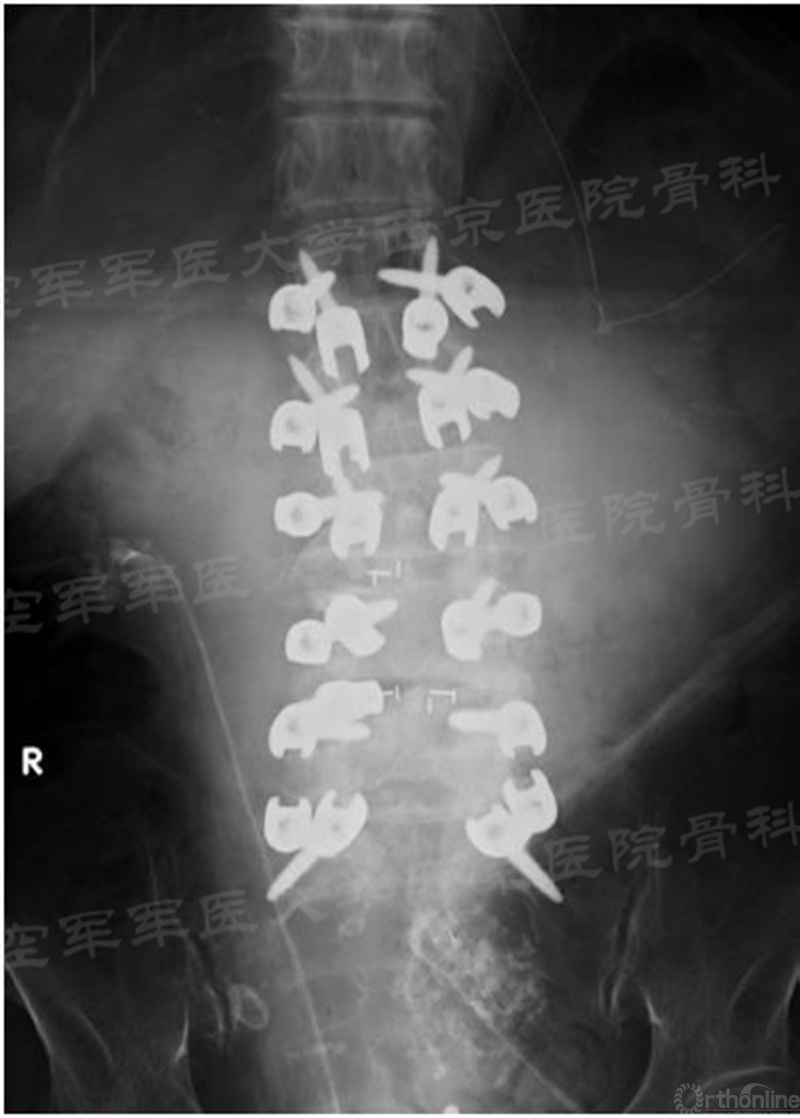

2009年,Santoni等首次提出了椎弓根皮质骨轨迹(cortical bone trajectory,CBT)螺钉固定技术。和椎弓根螺钉比,CBT螺钉固定的进钉点更偏内侧且钉道和皮质骨接触界面更大,螺钉的路径远离神经根、硬膜,且远离前方的血管结构,同时具有把持力强、创伤小等优势(见下图)。

皮质骨螺钉在翻修手术中的独到优势:不必拆除内固定,多种置钉方式联合,它可以单独使用,也可以与椎弓根钉混合或联合使用,两种螺钉联合使用方式具有最强的力学性能。